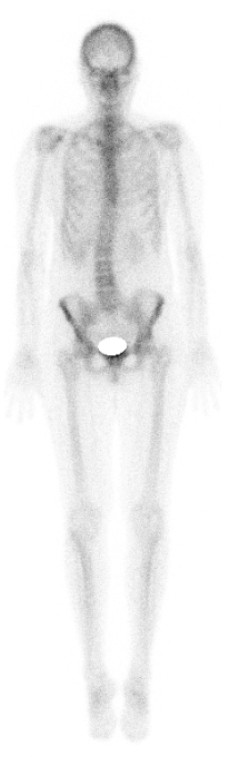

Knochenszintigraphie

Die Knochenszintigraphie ist in der Lage verschiedene Fragen beantworten. So kann nach Knochenmetastasen verschiedener Tumoren gesucht werden. Aber auch entzündliche Gelenkveränderungen bei unterschiedlichen Erkrankungen vor Therapie oder zur Therapiekontrolle sind erkennbar (z.b. bei Psoriasis oder auch aktivierten Arthrosen). Weiterhin können Materiallockerungen bei künstlichen Gelenken erkannt werden. Hier profitiert die Methode durch die hier genutzte Hybridbildgebung mittels SPECT/CT aufgrund der gesteigerten Genauigkeit erheblich, auch lassen sich überflüssige Mehruntersuchungen vermeiden.